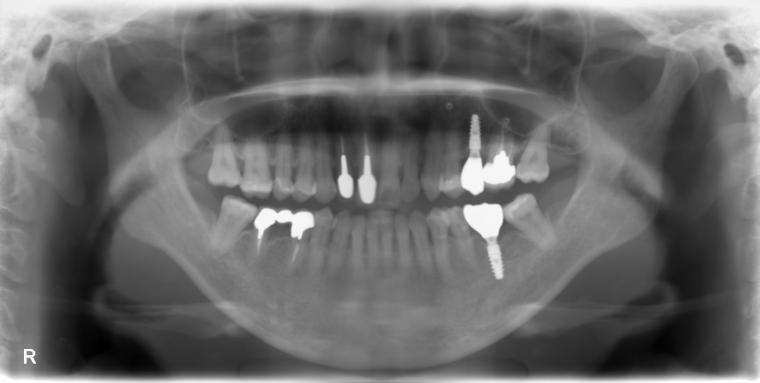

58歳女性/上下2本欠損/インプラント埋込手術

左上第二小臼歯が欠損状態で、インプラントのご相談でご来院された患者さんです。

左下第一大臼歯も、根っこの先で炎症が広がっており、抜歯後に左上と一緒にインプラントを埋入しました。